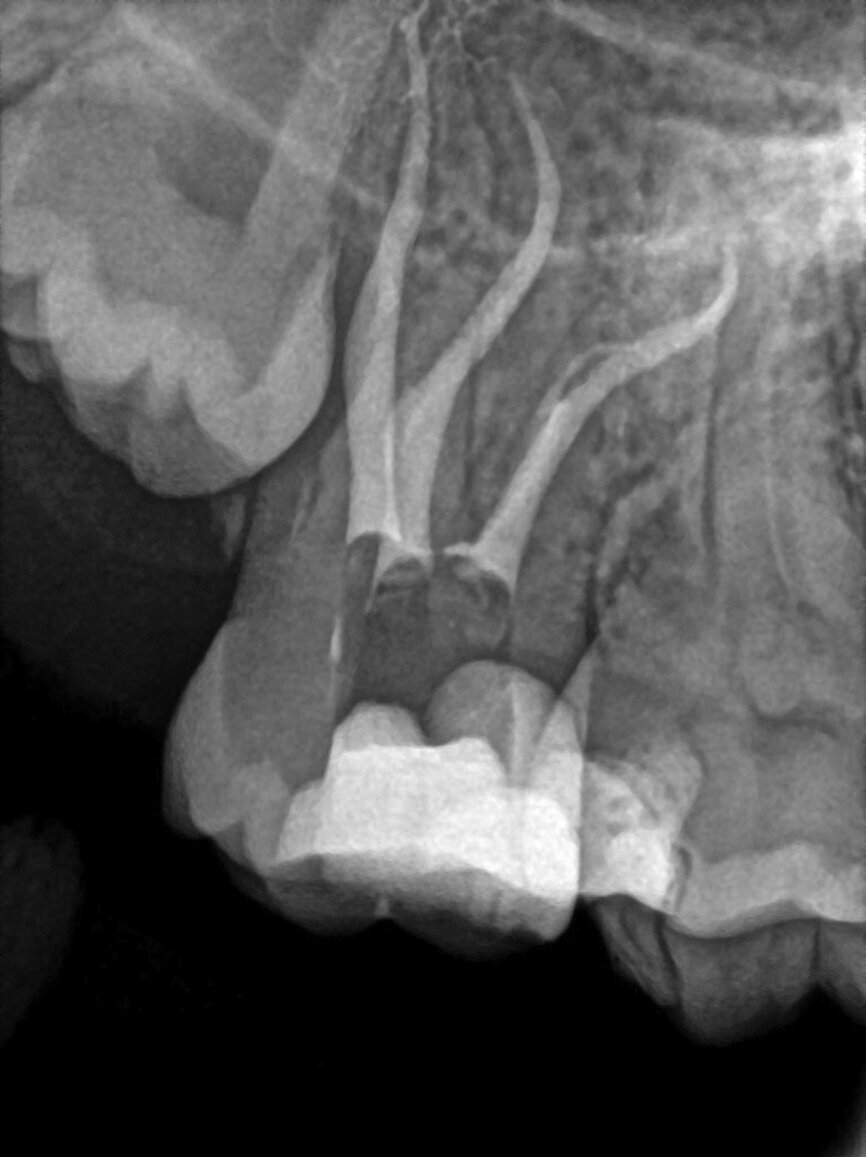

The patient, a 25-year-old female, reported with irreversible pulpitis on her maxillary second left molar. The tooth was temporarily restored with Intermediate Restorative Material (IRM, Dentsply Sirona) and the patient complained about continuous food impaction between her maxillary left, first and second molar teeth (Fig. 2). A periapical radiograph revealed that the temporary restoration was not sealing at the gingival margin (Fig. 3). Also, visible on the periapical radiograph was evidence of possible curvatures in the mesiobuccal and distobuccal roots. It was decided, with the consent of the patient, to take a limited field of view CBCT scan to explore the anatomy of this tooth. The CBCT scan revealed the presence of three root canal systems when viewed in the axial plane; and in the sagittal plane, evidence of severe root curvatures were present in the mesiobuccal and distobuccal root canal systems. It was decided to do a more in-depth investigation as a result of this complex anatomy, using the 3D Endo Software (Dentsply Sirona).

Fig. 3: Preoperative periapical radiograph showing a temporary restoration with poor marginal seal at the gingival margin.